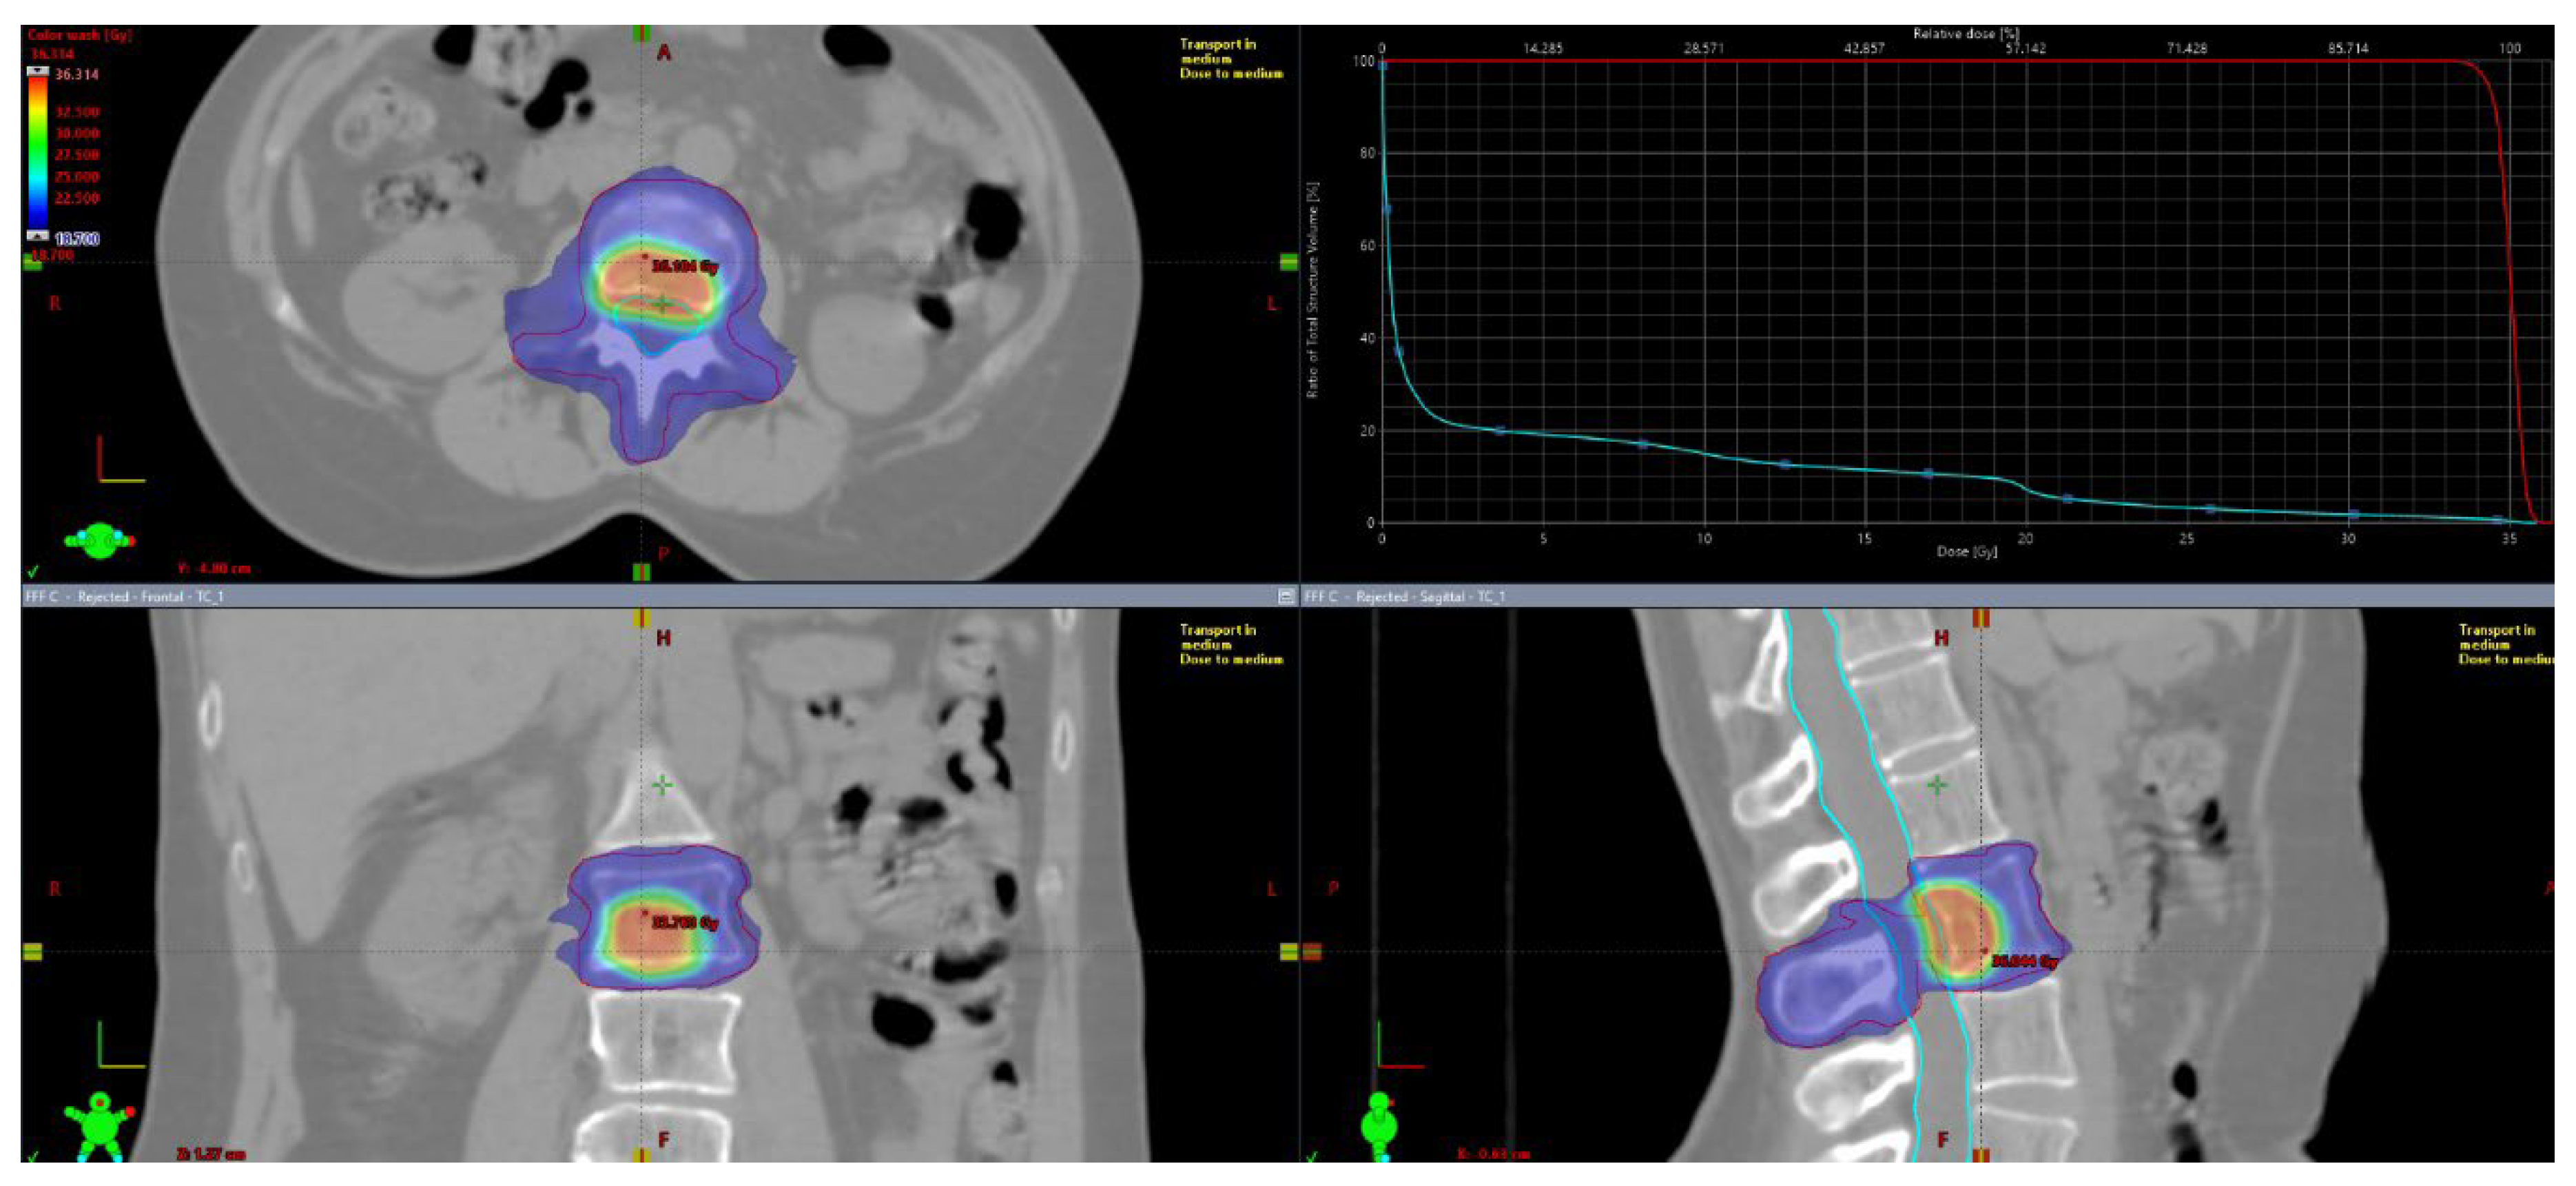

Patients underwent CT simulation with custom immobilization support (Aquaplast® head mask and/or vacuum mattresses). For target delineation, co-registriation with instrumental diagnostic exams (CT with iodine contrast, PET/CT and MRI) was mandatory. Gross tumor volume (GTV) was defined as the visible lesion at diagnostic exams. There was not a dimensional criteria of macroscopic disease visible at instrumental exams used for contouring. “Macroscopic” disease was identified as visible lythic or sclerotic or mixed lesion at II level (CT scan, PET-TC, MRI) used for delineation of planning target volume (PTV)1. Contouring defined two volumes: PTV1, including GTV plus 2-millimeters (mm) margin and PTV2, including entire bone compartment (for long and flat bones in the shoulder or pelvic girdle: the entire bone; for vertebrae: the entire vertebra) plus a 2-mm isotropic margin. For vertebral lesions both spinal canal and spinal cord were contoured. Organ at risks were contoured based on lesion’s site and dose constraints were mantained according to AAPM reports [8]. The planned doses ranged from 20 to 30 Gy for PTV2 with several fractions from 3 to 10 in according to clinical practice. Three different SIB doses were delivered to PTV1 (35, 40 and 50 Gy). PTV1 coverage was set at 95% of the prescribed dose at 95% of the defined volume. Major deviation for PTV2 was < 77% of the dose prescribed at 95% of the volume, while minor deviation was < 84% of the prescribed dose at 95% of the volume. For PTV1, major deviation was defined as < 79% of the prescribed dose at 95% of the volume, while minor deviation will be < 84% of the prescribed dose at 95% of the volume. Normalization of PTV1 was at 80% of prescribed dose, so inside lesion it was provided also a gradient of heterogeneity since to 120-125% of prescribed dose. Reporting of dose prescription will be done according to International Commission on Radiological Units (ICRU) 83. A representative figure of treatment plan is reported in Figure 1. Treatment plan reporting was according ICRU 83.

Figure 1. Treatment plan of a SIB-IMRT treatment.